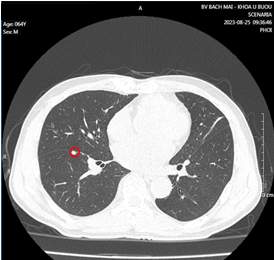

- Cắt lớp vi tính lồng ngực có tiêm thuốc cản quang:

Hình 1. Khối u kích thước 51x58x42mm thùy trên phổi trái, ngấm thuốc không đều sau tiêm (vòng tròn đỏ).

Hình 2: Vài nốt đặc nhu mô phổi 2 bên, kích thước lớn nhất 5x6mm